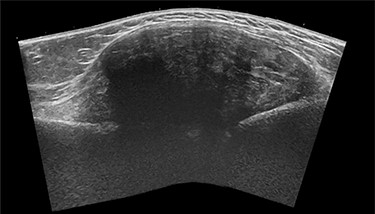

The general practitioner ordered an ultrasound (US) of the upper arm. US showed a sharp delineated fusiform mass (CC 8.5 × LL 6.5 × AP 3 cm) with heterogeneous echogenicity, associated with the lateral humeral cortex beneath the deltoid muscle (Fig. 1). The mass showed limited internal Doppler signal. A soft tissue tumor such as a sarcoma or desmoid was suspected, and magnetic resonance imaging (MRI) was advised.